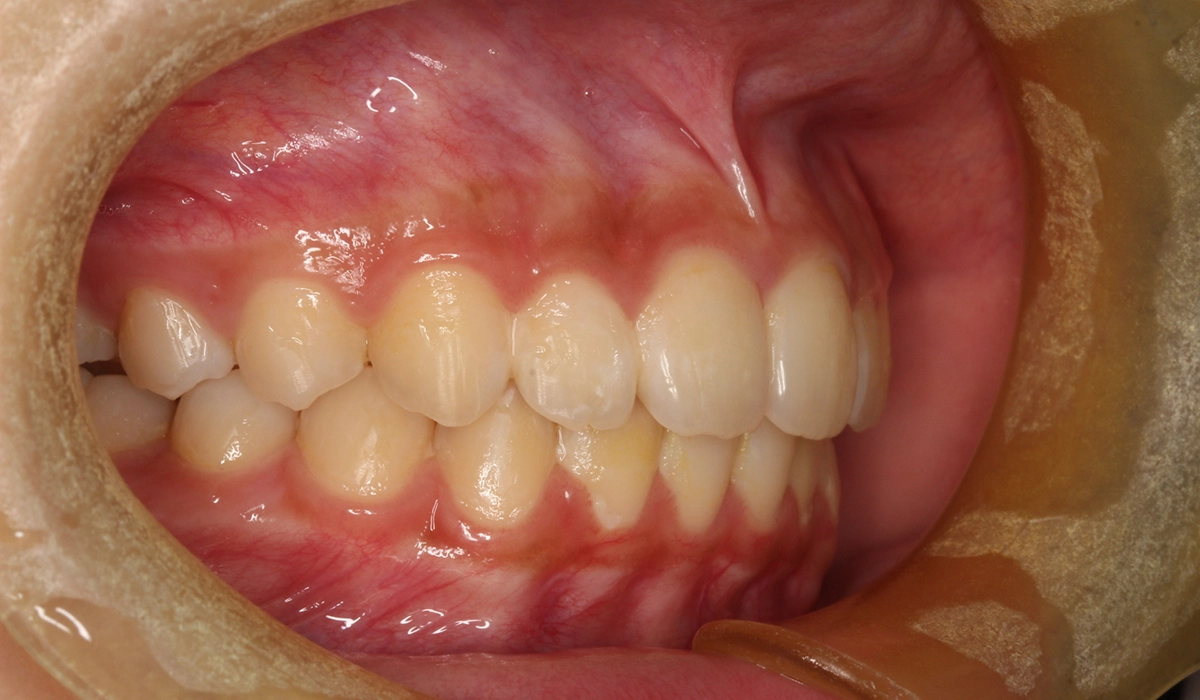

術前:左側

術後:左側